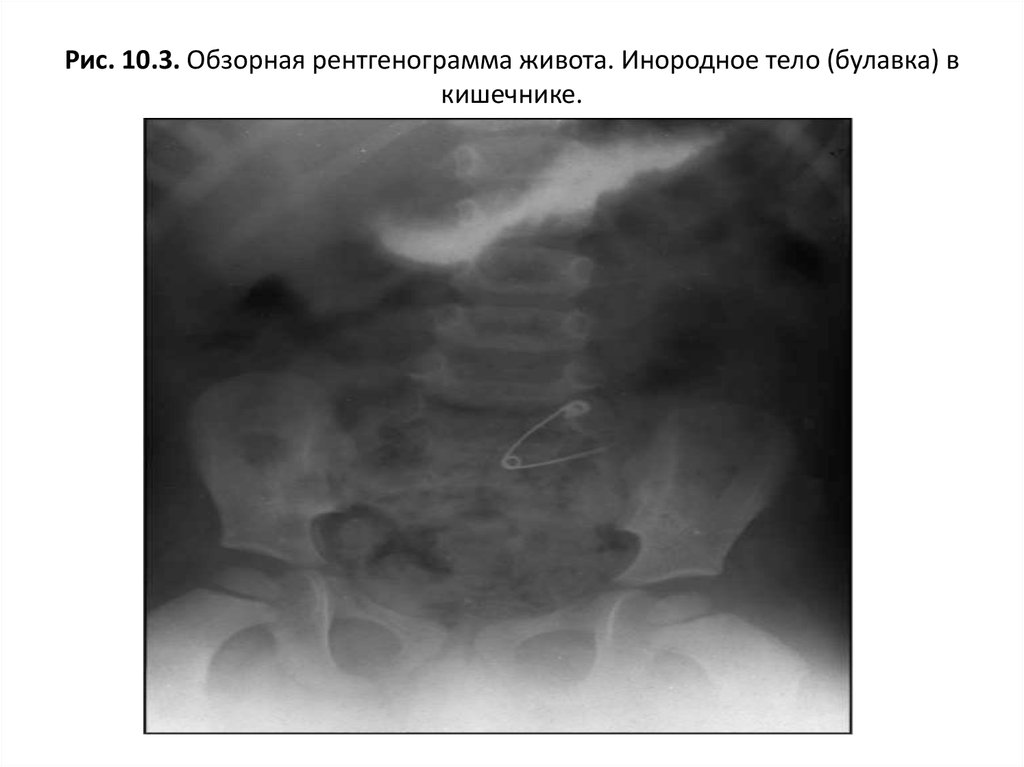

Существуют инородные тела рентгеноконтрастные – они визуализируются на рентгене, и не рентгеноконтрастные – они не визуализируются на рентгене (например, дерево). Дополнительное введение рентгеноконтрастных веществ (сульфат бария, йодсодержащие препараты), при проведении рентгена пищевода и желудка, позволяют в некоторых случаях определить не рентгеноконтрастные инородные тела (фото 1).

- Рентгенография – позволяет рассмотреть петли тонкого кишечника, располагающиеся в центральной зоне брюшной полости в двух проекциях – вентродорсальная и боковая. Аномальное расширение исследуемого материала сигнализирует о растяжении от постороннего предмета или от иных причин. На снимке можно обнаружить металлические вещи, кости, камни, стекло. Впрочем, не всегда инородные тела видны с помощью рентгенографии. Так, сложно обнаружить на снимке нитки, резиновые изделия, полиэтилен или тряпку. В этом случае применяют контрастную рентгенографию или другие способы исследования.